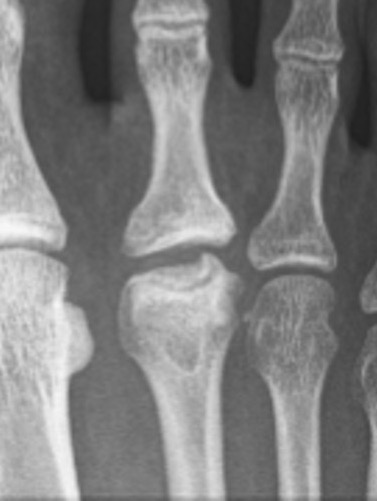

X-ray

Enlarged metatarsal head

Flattening / fragmentation / collapse

Smillie Classification

Stage 1 - normal xray, MRI positive

| Stage II | Stage III | Stage IV | Stage V |

Slight widening of joint space Sclerosis of epiphysis |

Flattening of epiphysis

Fragmentation of epiphysis Multiple loose bodies |

Osteoarthritis |